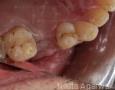

3 Months

4 Months

6 Months

1 Year